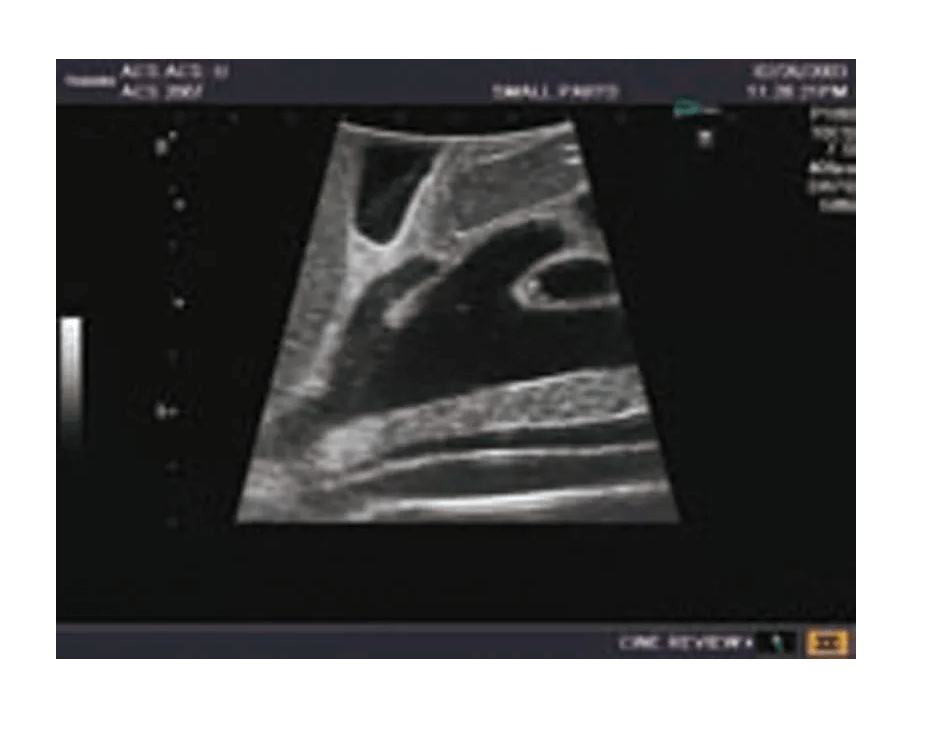

Das Ultraschall-Modell für Sonografie ist speziell für die Ausbildung von Anfängern und die Demonstration durch Fachleute konzipiert. Es bietet eine detaillierte und realistische Darstellung der Anatomie des Abdomens, einschließlich der Leber, Gallenwege, des Pankreas und der Nieren. Das Modell erfüllt die höchsten Anforderungen an eine exzellente Ausbildung und ermöglicht die Durchführung von offenen intraoperativen Sonografien sowie laparoskopischen Untersuchungen, um etwaige Läsionen und Steinbildungen zu prüfen. Es umfasst eine Vielzahl von Läsionen wie Gallensteine, Zysten und Tumore, die in den verschiedenen Organen simuliert sind, um realistische Übungsmöglichkeiten zu bieten.

Simulierte Läsionen (solide Tumore, Zysten, Gallensteine) in wichtigen Organen für praxisnahe Ausbildung

Integrierte Simulation von organischen Läsionen und Tumoren, die in die Organe eindringen, für die Übung und Diagnostik

Die Simulation von pathologischen Befunden wie Tumoren, Zysten und Steinbildungen ermöglicht eine umfassende Vorbereitung auf die Ultraschalldiagnostik